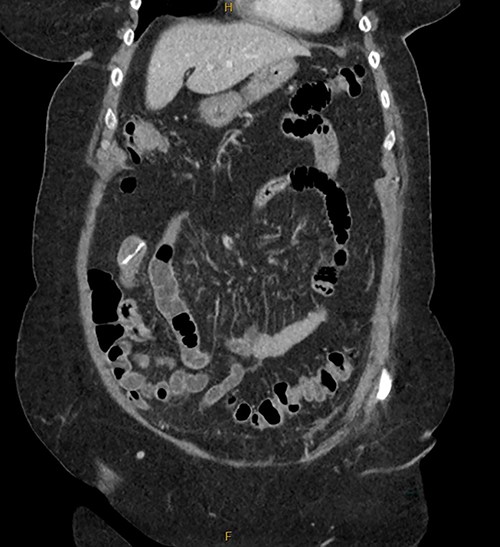

Patient SC is a 72-year-old lady who presented with urosepsis secondary to a left-sided distal ureteric renal stone. Her medical history includes ischemic heart disease, chronic pulmonary obstructive airway disease, type 2 diabetes mellitus, Parkinson’s disease and a previous open cholecystectomy. She was admitted to the intensive care unit and a left-sided nephrostomy tube was inserted. Initial CT imaging incidentally identified a ‘bread clip’-shaped FB in the distal jejeunum (Figs 1 and 2). There was no evidence of obstruction nor perforation. Abdominal X-rays failed to show the presence of a FB.

The acute surgical unit team consulted the patient and initial conservative management included keeping a stool diary and trialling 1 L of glycoprep. Unfortunately, serial imaging failed to show any meaningful progression of the FB. After a successful antegrade ureteric stent insertion, the patient recovered from urosepsis and a decision was made to proceed with a laparoscopic small bowel resection to retrieve the FB.

Intraoperatively, an inflamed segment of 5 cm of the mid jejunum was identified, the FB was palpable and appeared to be partially eroding through the serosa. A SB resection was performed with primary stapled anastomosis. The FB was identified as a BC.

Secondly, as shown in the three cases, unless the BC is calcified, abdominal plain films are not a reliable method of tracking nor diagnosing BC ingestion [9–13]. CT is more sensitive, with a sensitivity rate of 67%, but is not consistently reliable on its own [6, 7]. Reconstructed 3D imaging is effective in identifying BCs. Most BCs are made of low-density polystyrene, a type of versatile solid plastic, which are not readily identified on plain film imaging [14, 15]. This non-degradable plastic means that it is usually only a matter of time before a patient develops a complication.